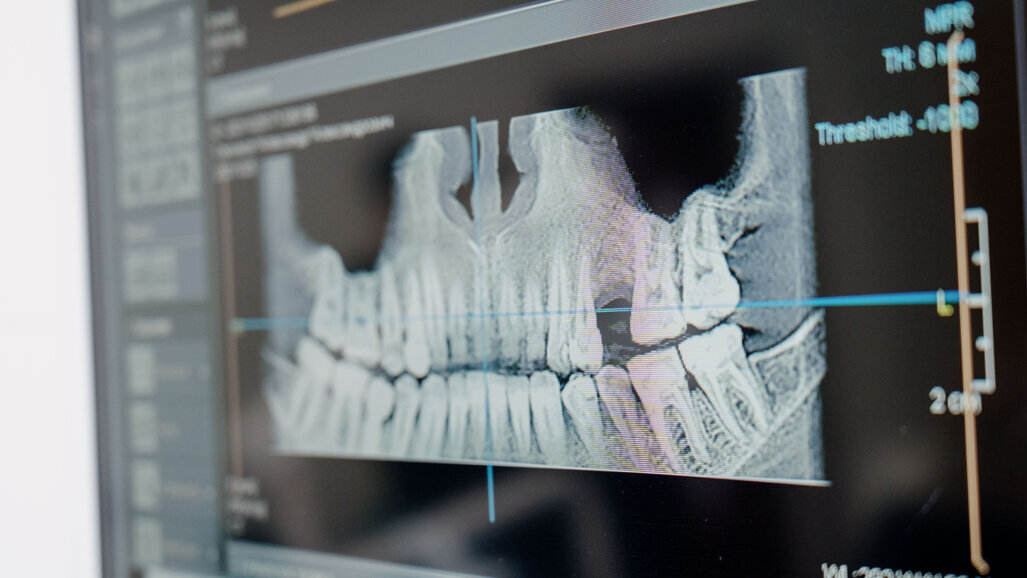

Atualmente, conseguimos realizar diagnósticos rigorosos através de um trabalho dividido entre o ortodontista e a IA: análises cefalométricas, avaliação de TAC, análise de modelos, avaliação de tecidos moles são, hoje, realizadas de forma eficiente e com rigor científico através da IA, sendo que cabe ao ortodontista a análise de dados e a sua interpretação. Ao utilizar dados de pacientes facilmente disponíveis, os médicos dentistas já estão a utilizar softwares que reúnem informações pormenorizadas para a tomada de decisões clínicas. Estes programas integram algoritmos de IA que permitem aos médicos dentistas e ortodontistas disponibilizar os melhores cuidados aos seus pacientes, ao tornar os resultados dos tratamentos mais previsíveis, sob supervisão médica.

Na minha opinião, o futuro da ortodontia passa por dois tópicos: o tratamento ortodôntico com aligners transparentes, que substituirá os tradicionais brackets, e o diagnóstico exaustivo com CBCT, scanner, vídeo e fotografia que fará parte do planeamento de todos os casos.